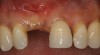

A 45-year-old woman presented with a narrow edentulous ridge in the maxilla (Figure 1). Following adequate anesthesia, a horizontal incision palatal to the crest and two vertical incisions were placed to outline the surgical field. A periodontal probe was used to measure the width of the alveolar crest at the most coronal dimension after a full-thickness flap was elevated (Figure 2). From the author’s experience, it was not necessary to maintain palatal bone-periosteum.